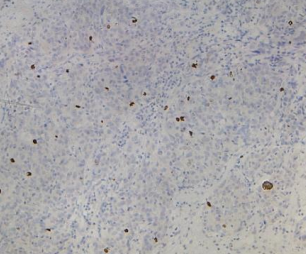

脑胶质细胞瘤用 NeuN(GT2194)染色,肿瘤细胞胞核着色,DAB显色